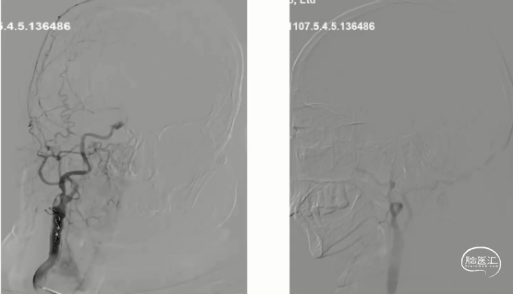

HR-MRI:右侧颈内动脉起始处偏心斑块,管腔重度狭窄,增强可见明显强化

HR-MRI:

3D-SPACE示,①右侧颈内动脉、右侧大脑前动脉A1段、右侧大脑中动脉管壁增厚,考虑动脉粥样硬化并不稳定斑块形成可能,②左侧颈内动脉交通段、左侧大脑中动脉、双侧大脑后动脉、双侧椎动脉V4段动脉粥样硬化改变,以上,请结合临床及其他检查协诊